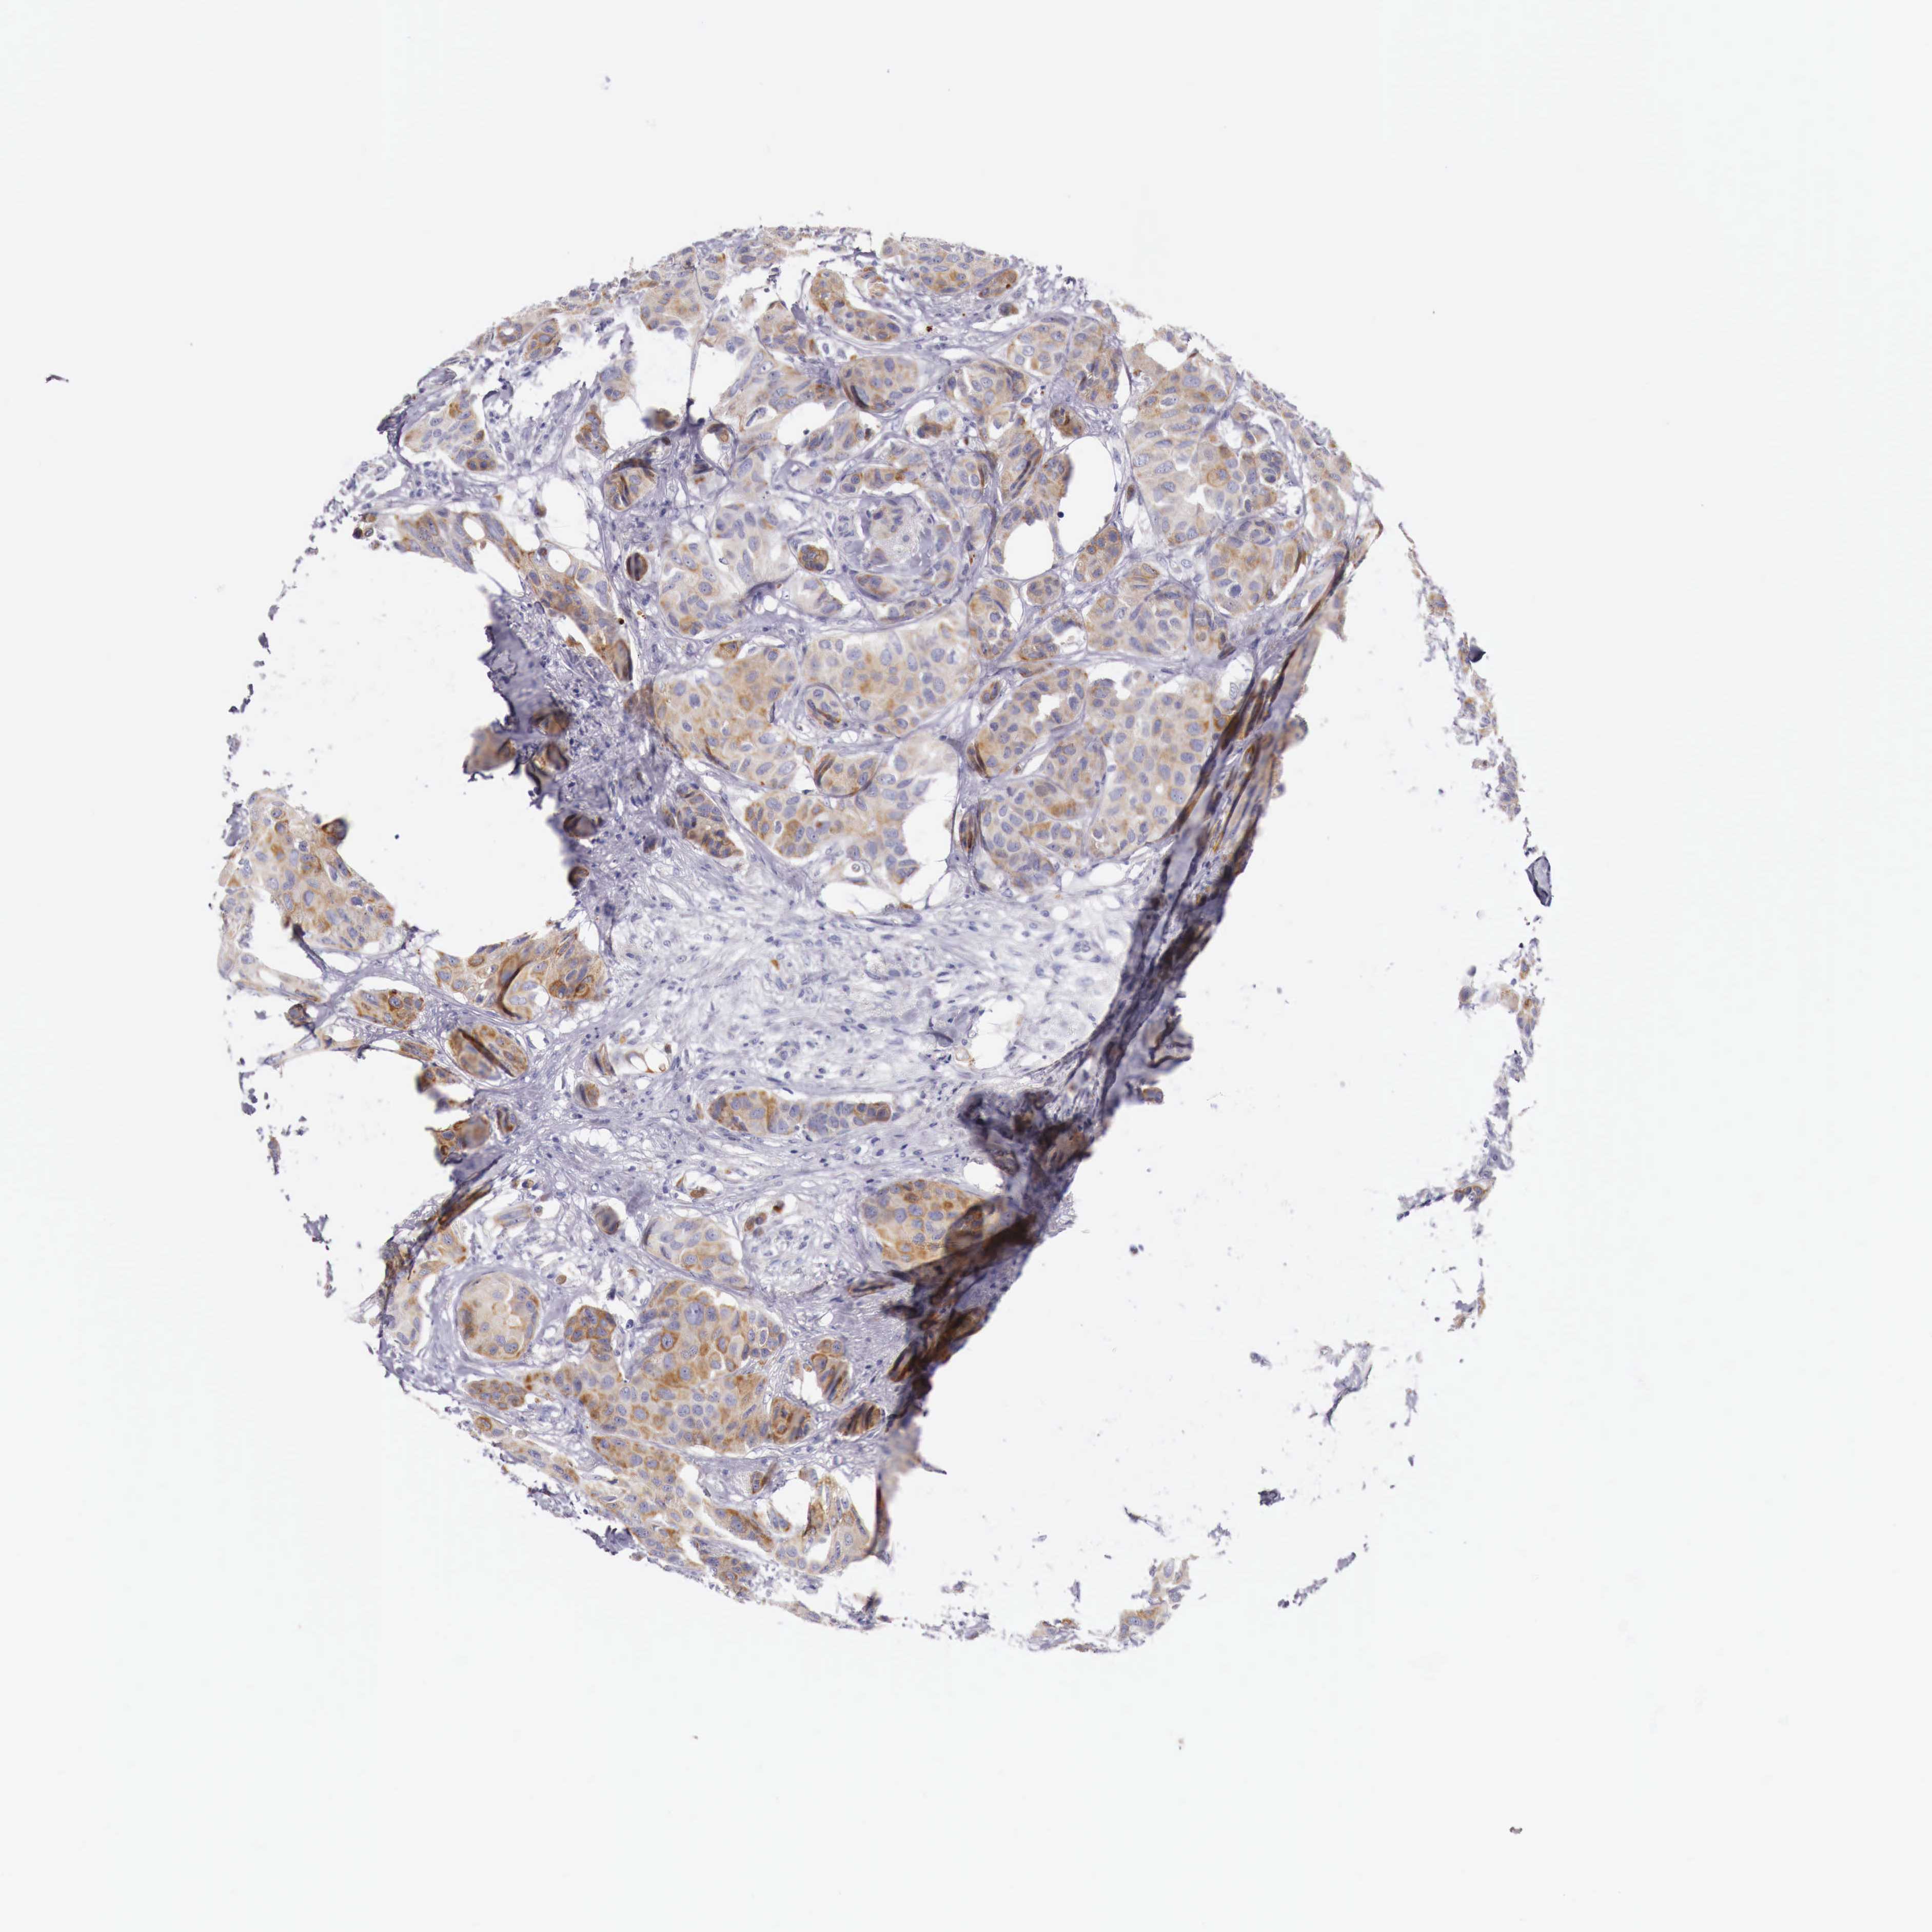

CANCER BREAST CANCER Show tissue menu

BRCA TCGA BRCA VALIDATION PROTEIN EXPRESSION